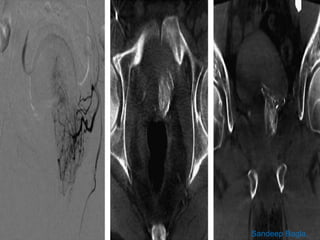

The prostate gland is a pyramid-shaped organ that weighs approximately 20 grams and measures 3x4x2 cm. It has three zones - the peripheral zone (70%), central zone (25%), and transitional zone (5-10%). Prostate cancer develops in the peripheral zone, while benign prostatic hyperplasia (BPH) develops in the transitional zone. The prostate receives its blood supply from various arteries, most commonly the internal pudendal artery (34%). Knowing the detailed arterial anatomy is important for procedures like prostate artery embolization (PAE) to treat conditions like BPH and prostate cancer. Imaging tools like CT angiography and cone beam CT can help the interventional radiologist map the arterial supply before